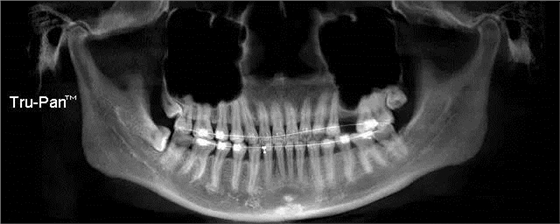

第二圖:上頜竇氣化,導(dǎo)致上頜竇很大,骨高度不足,但是上頜竇底平,粘膜很干凈。適合外提升或者高手可行內(nèi)提升。(還有二次內(nèi)提升)。